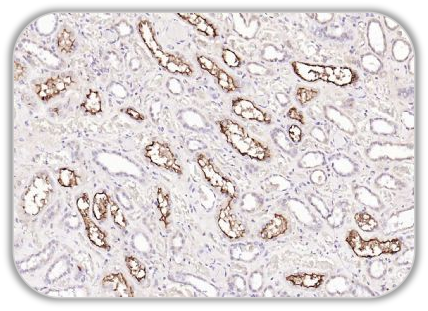

Anti-ACE2 Antibody (bs-46001R)

IHC Human Kidney